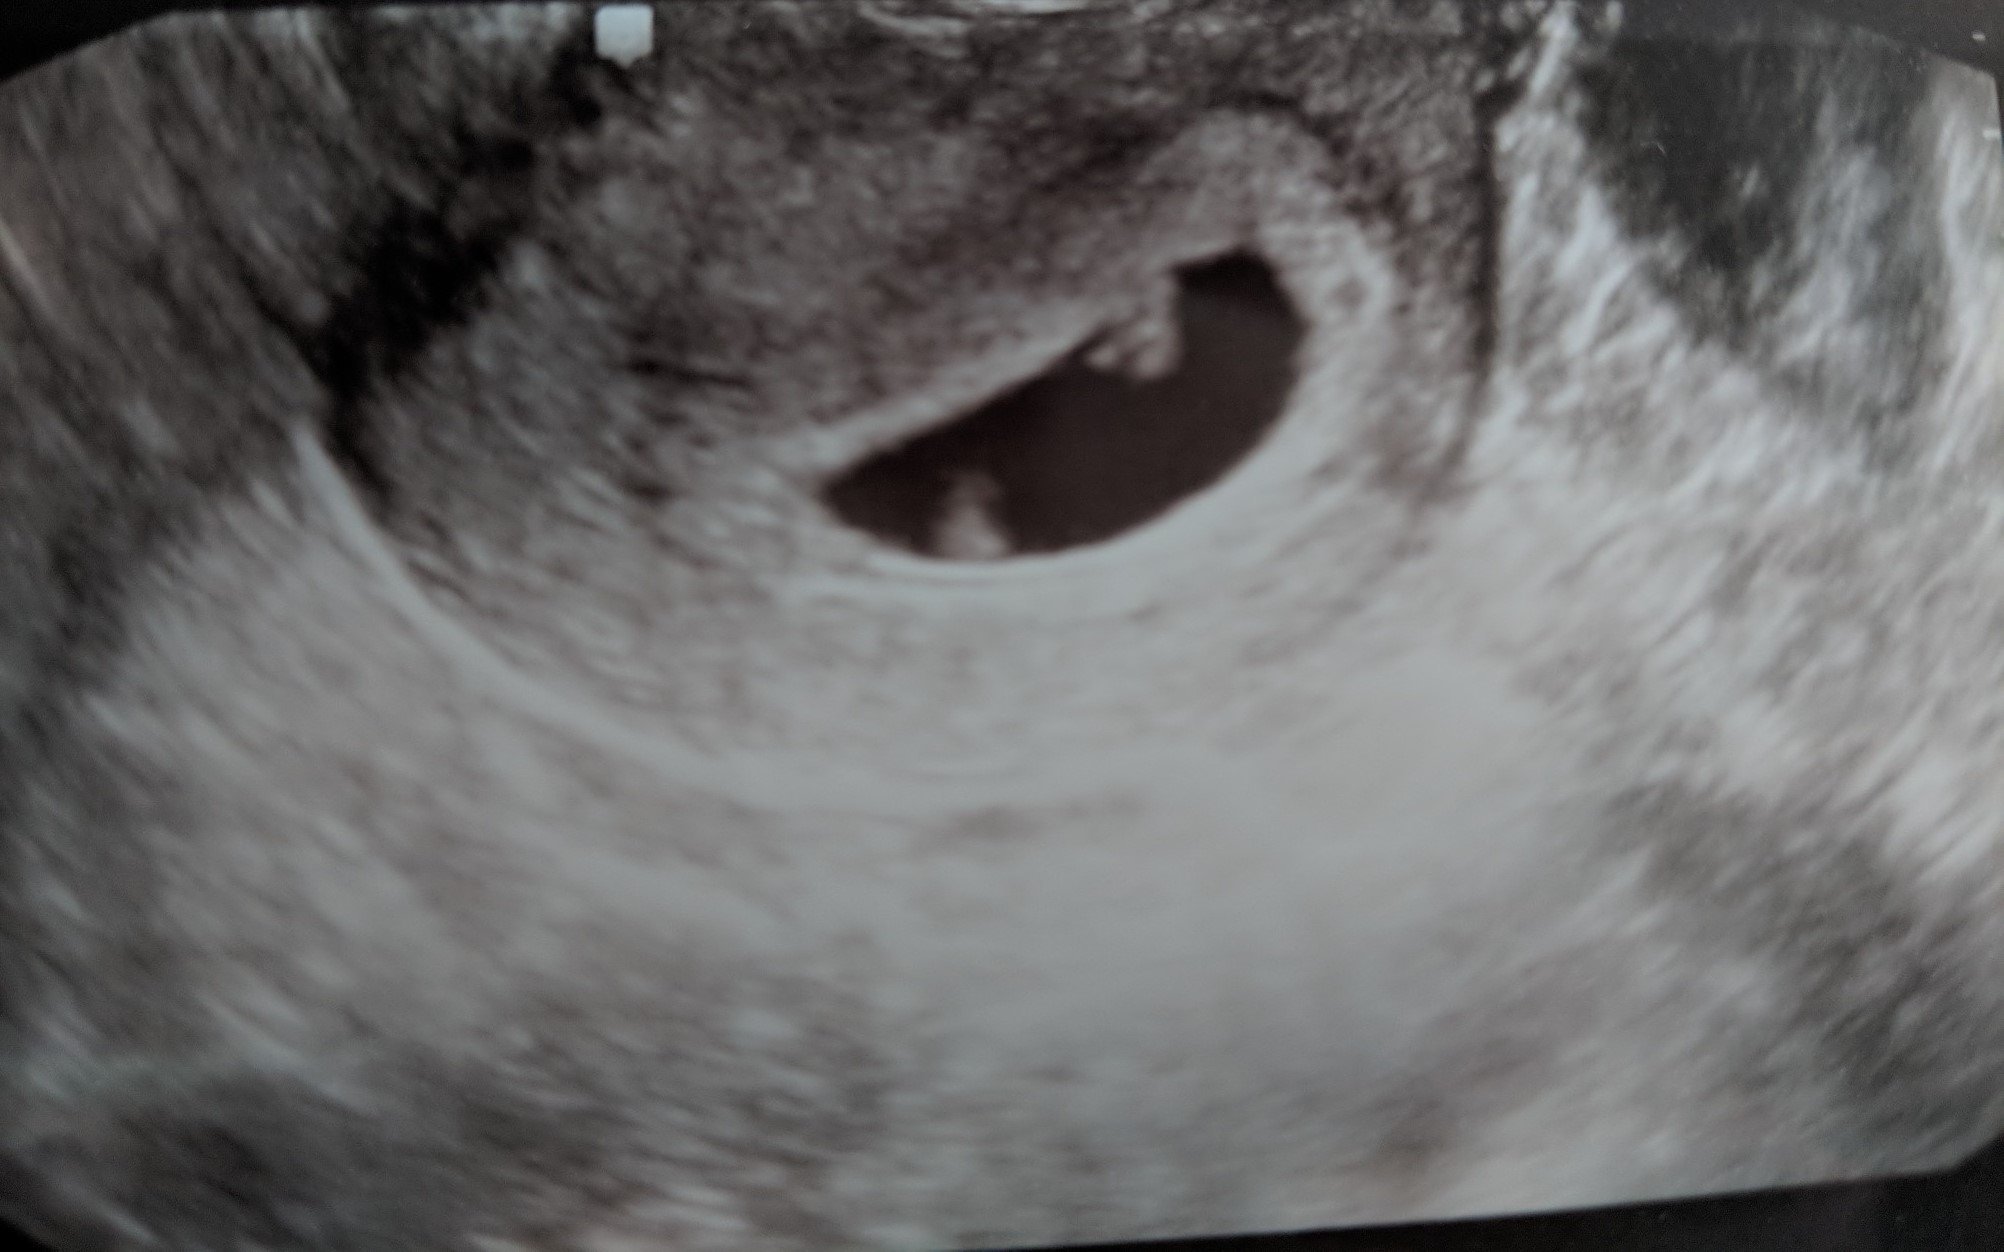

Today was so hard for me. This was our big milestone ultrasound in my mind bc we’ve never gotten this far and I just went in fully expecting bad news. It really made me realize how effed up I am in the head from all of this. BUT. Everything was perfect. She even let us hear the heartbeat which was a surprise because they don’t normally do that at our practice and it was so much more amazing than I could have imagined it would be. And getting to see my husbands face when he heard it was just...sigh. Measuring 8 weeks exactly and working hard on those tiny arms and legs! I have two more with my RE and then pick right up with my OB after that, so grateful to not have a gap in care the time around!